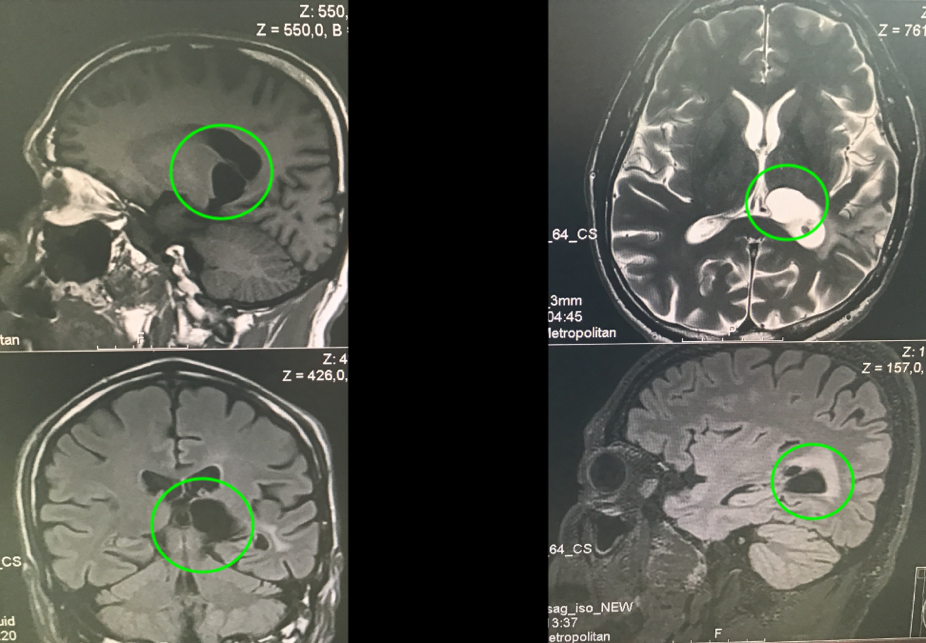

作为钢琴演奏家、钢琴老师的Z女士,大约4个月前发现出右手弹奏不灵活,细致活动限制,头部右侧和右脚麻木感,也偶有视力模糊、有雾感,起初本以为是太劳累所致,却不见好转,当地医院就诊,在当地医院发现丘脑内较大占位,考虑胶质瘤可能。Z女士而后辗转多处,得知德国Helmut Bertalanffy(巴特朗菲,国内病人尊称“巴教授”)在这领域的丰富成功经验,成功联系并进行了二意见咨询,得到可以手术全切的回复后,一家人带她前往巴特朗菲教授所在的德国汉诺威INI国际神经学研究所进行手术治疗。

在5-ALA荧光、术中神经导航和术中MRI辅助手术,通过左侧顶枕枕骨开颅术和显微外科肿瘤全切手术,手术顺利,无手术并发症。患者术后当天即拔出气管插管,无任何问题,转入重症监护室进行观察1天。术后当天与术前相比,右手和手臂仍有轻微的偏瘫和轻度运动无力,无言语功能障碍。术后2天,检查术后CT正常,无血肿和明显脑水肿等,该患者的临床状况迅速好转,并迁出ICU。术后3天即在物理治疗下增加康复锻炼,下地锻炼,术后5天即可自行站立行走。在INI住院期间,手细致功能障碍、言语和感觉偏瘫均得到好转。右手的细致运动技能也比手术后开始时明显好转。